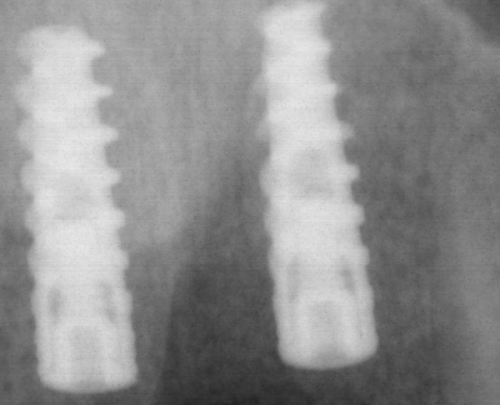

糖尿病患者和吸烟者是感染的高危人群。当糖尿病患者的糖化血红蛋白>7%时,感染风险会激增3倍;每天吸烟超过10支的人,骨结合失败率会升高2.5倍。曾经有一位患者,术后忽视了口腔清洁,在CT片上都能看到骨吸收形成的空洞。所以,手术前后一定要注意消毒和清洁,尤其是高危人群更要格外小心。